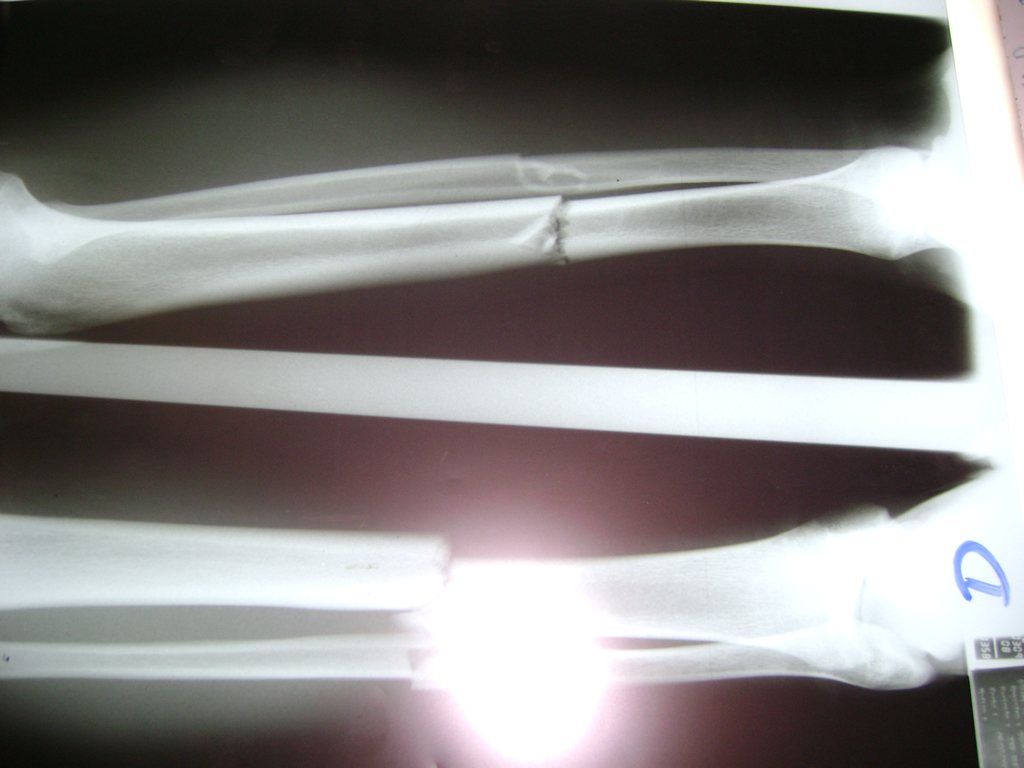

Húmero - Perone y Tibia

Aunque cada uno de estos huesos puede fracturarse por separado, normalmente la rotura es una lesión que se produce de forma conjunta

La mayor parte de las roturas implican a la parte proximal del hueso (parte del hueso próximo a la rodilla) o a la parte distal (parte del hueso cerca del tobillo).

Debido a la fina cobertura de piel que recubre la tibia y el peroné, las fracturas generalmente son abiertas, es decir, el hueso roto rasga la piel, atravesándola. Las fracturas de tibia y peroné generalmente se producen por un fuerte impacto o torsión.